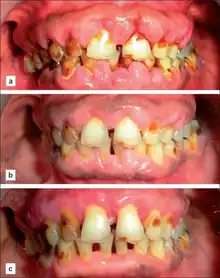

Amlopidine induced gingival enlargement (a) at first visit (b) ten weeks after phase 1 therapy (c) nine-month postoperative